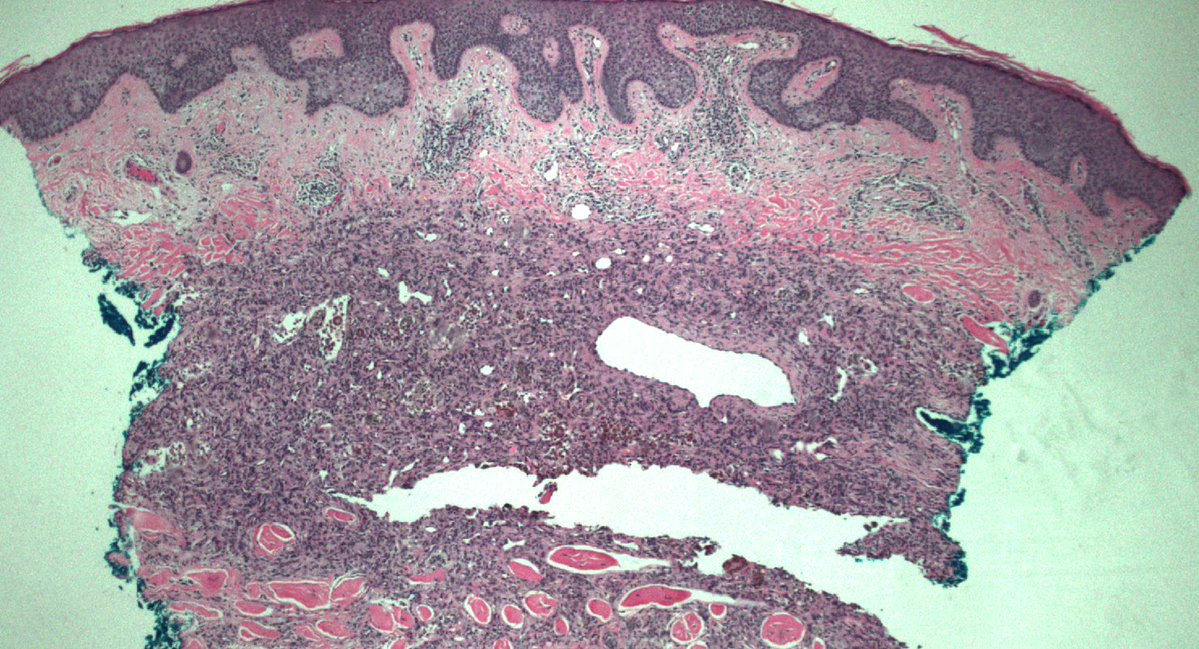

🚨Spoiler alert. What a delivery right before #USCAP2026! Our study on DPN-like melanomas, featuring a new, nonconventional pathway beyond CTNNB1 and APC mutations, will be online soon. Stay tuned! 😆🔬

#dermpath #MDACCPath #molepath 🧬